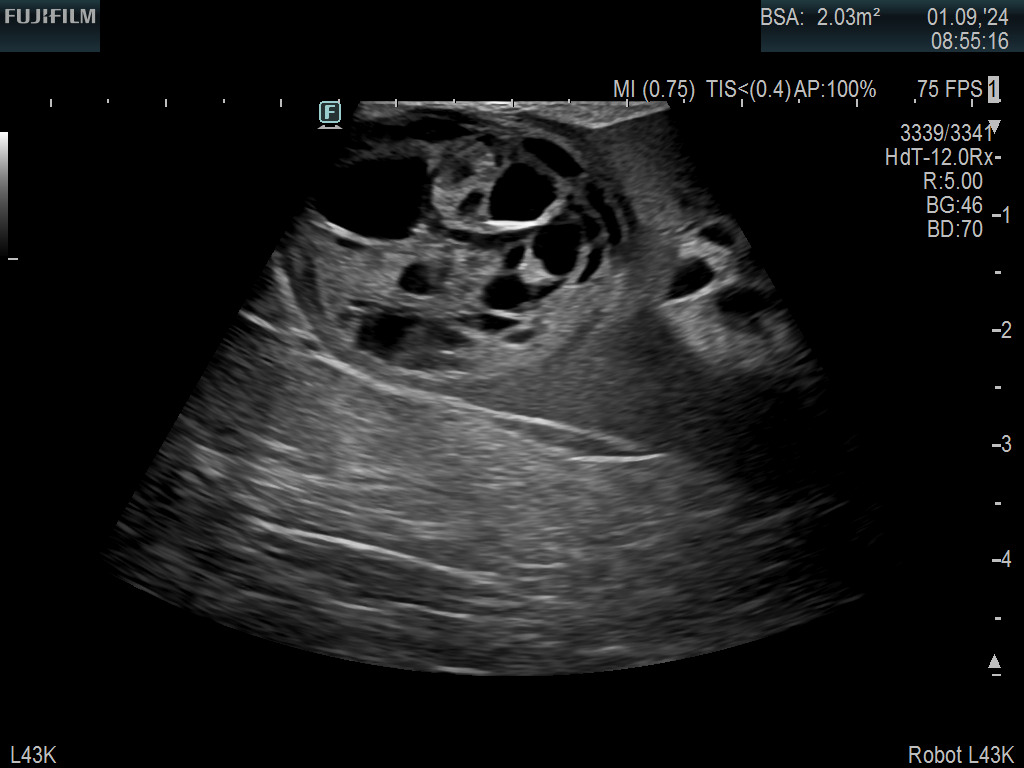

Exclusive 10mm side-fire linear array transducer with 2.87mm diameter is ideal for real-time visualization through and behind structures and instant, scalable definition of anatomy and vascularity including the ability to delineate and define tumor margins.